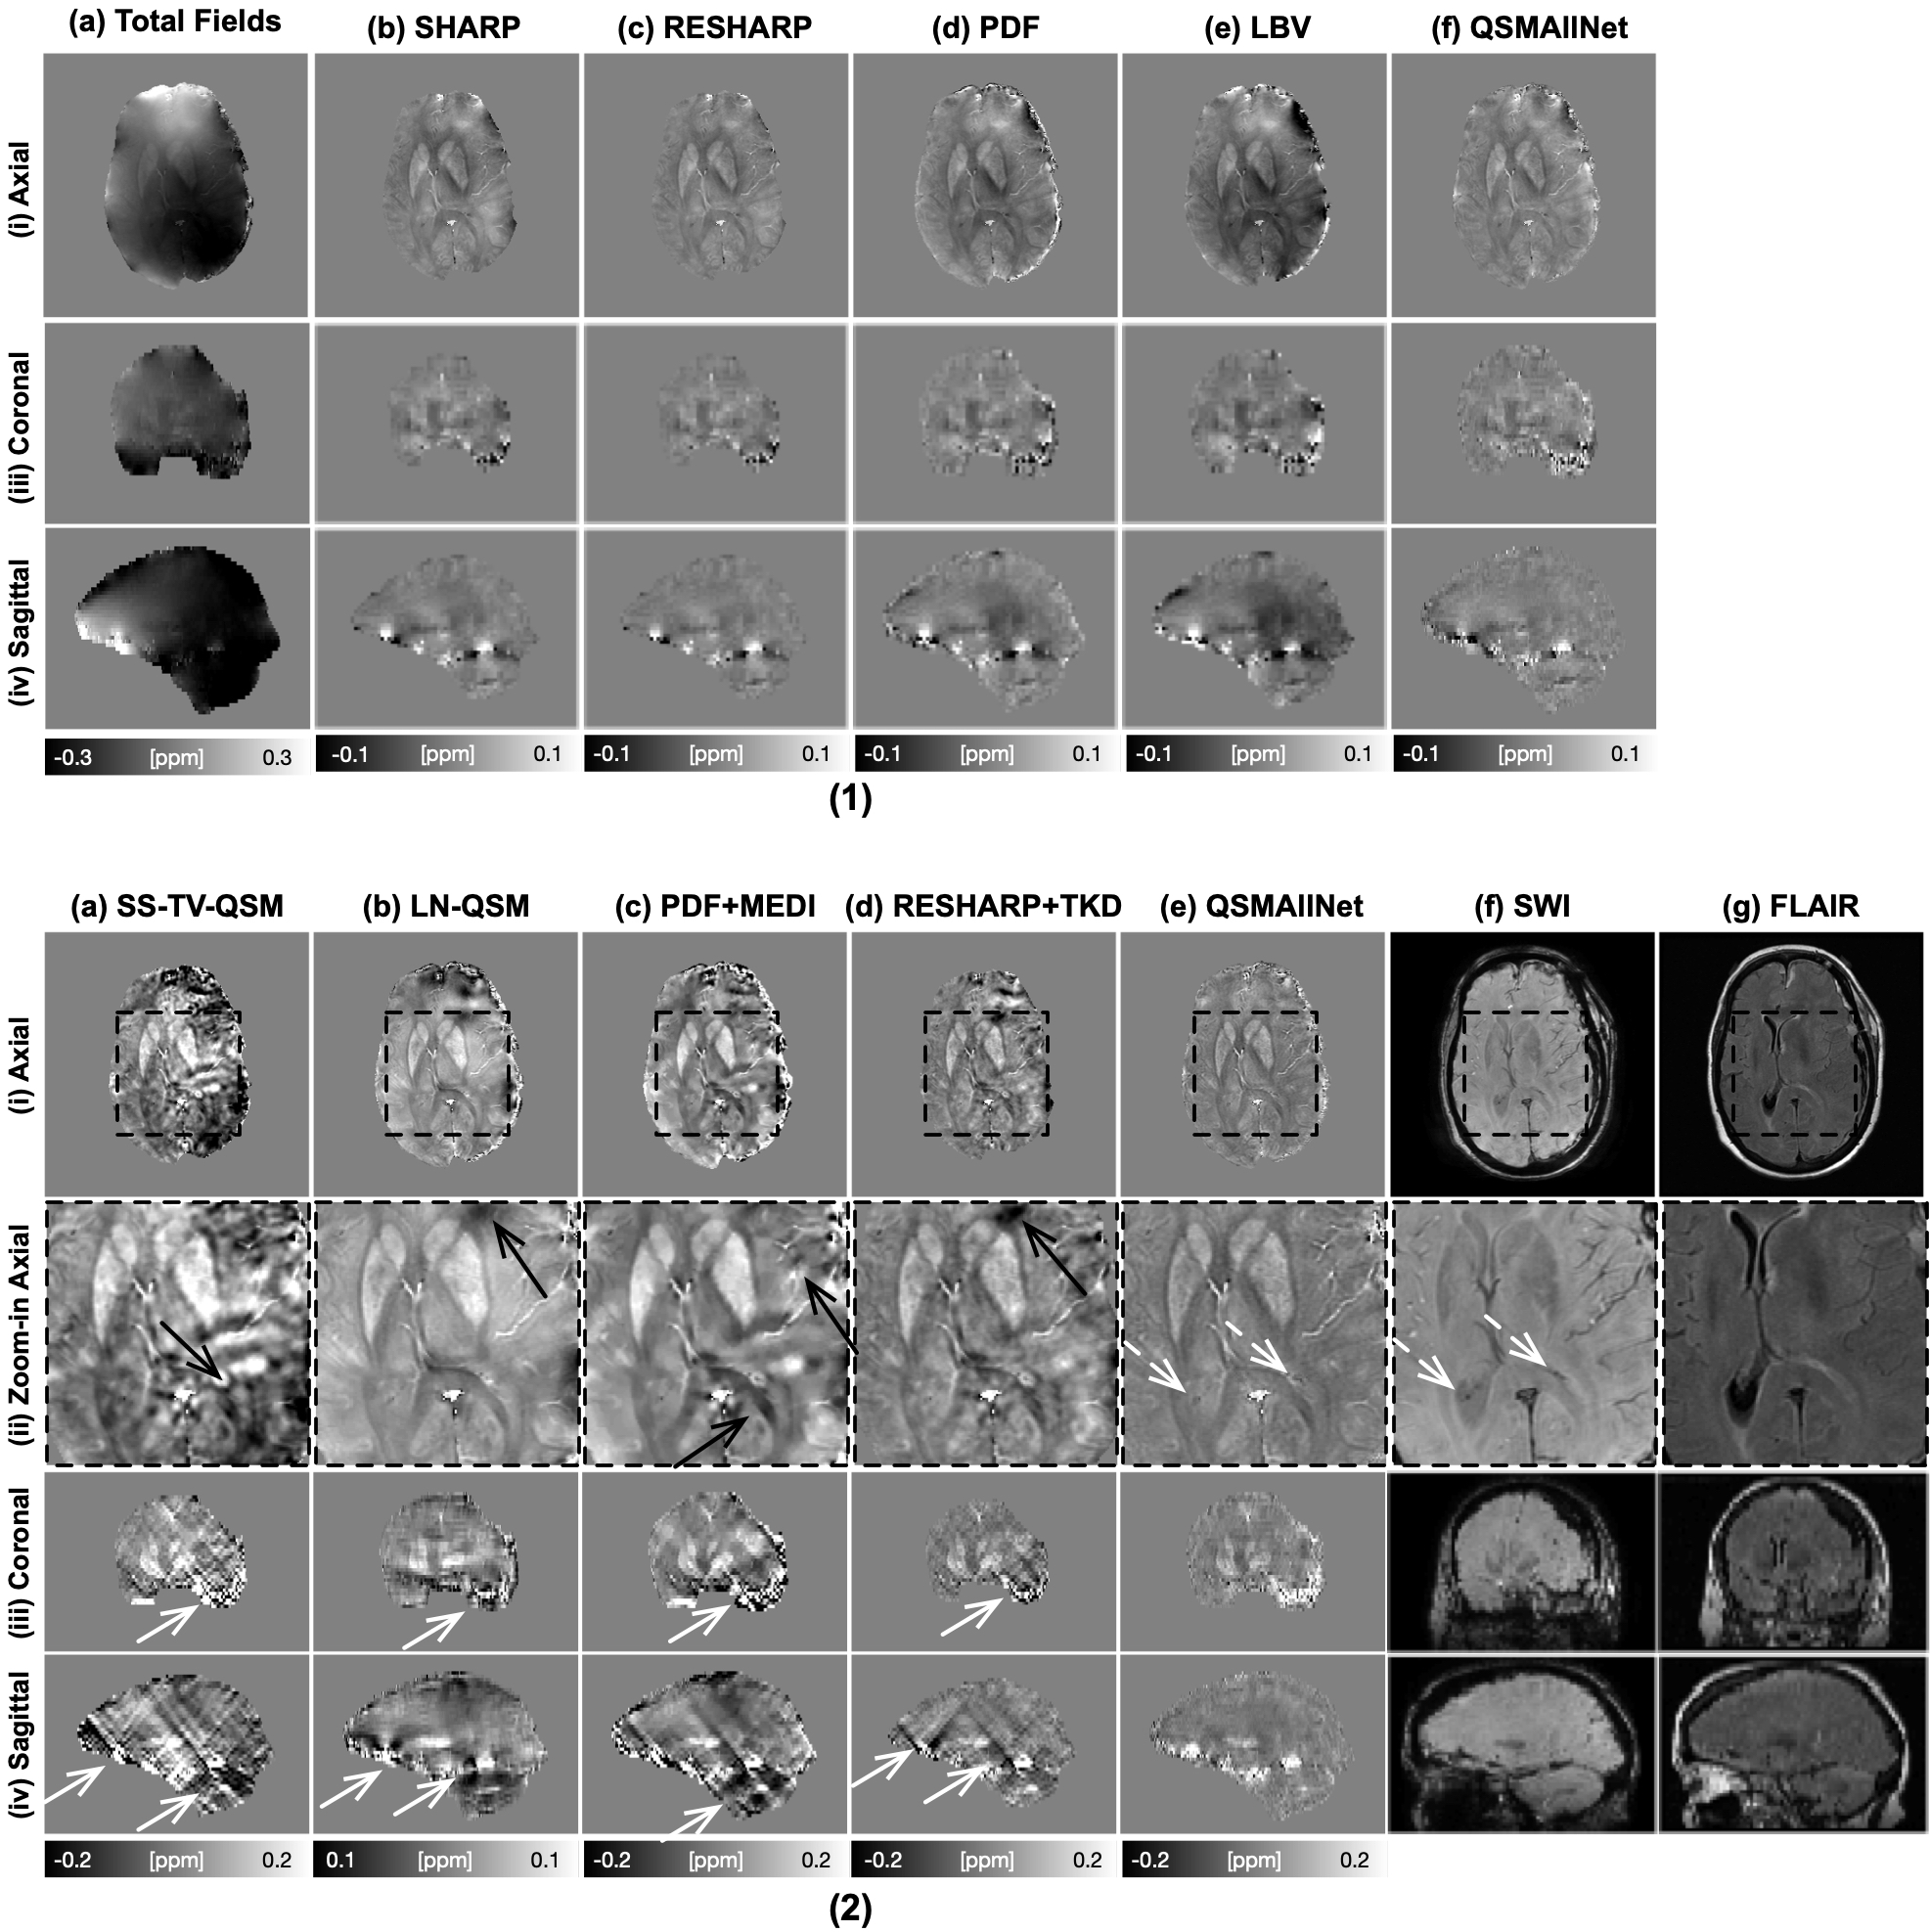

In Fig. 8, a 56-year-old subject with hemorrhagic intracranial metastases is illustrated. PDF and LBV results show obvious shading artifacts (1, d-e, i-iii). QSMAllNet shows invisible artifacts in the local field. From the QSM images, SS-TV-QSM, PDF+MEDI, and RESHARP+TKD suffers severe shading artifacts and streaking artifacts, as shown (2, a, c, d, i-iv). LN-QSM shows strong shading artifacts, as shown (2, b, i-iv). With comparison to other methods, QSMAllNet results (2, e, i-iv) showed improved image sharpness, clear tissue structures, and no shading and streaking artifacts around bleeding regions. Besides, two small calcifications are dark/hypointense on SWI images and diamagnetic on QSM images (white dash arrows, 2, e-f, ii).

Figure 8: Total fields and QSM background removal results (1), susceptibility images, SWI images and FLAIR images (2) on a 56-year-old subject with hemorrhagic intracranial metastases. In (1), residual background fields are clearly visible in SHARP, RESHARP, PDF and LBV (b-d) results in axial and saggital views. SHARP and RESHARP results (b-c) have brain erosion. LBV and PDF have shading artifacts in the tissue fields. QSMAllNet results show better background field removal. From the susceptibility maps (2), SS-TV-QSM, LN-QSM, PDF+MEDI, and RESHARP+TKD have susceptibility large estimation errors, especially streaking artifacts and shading artifacts (white arrows). Two small calcification is dark/hypointense on SWI image and diamagnetic on QSM images (white dash arrows). Based on visual comparison, QSMAllNet can produce improved local field and susceptibility estimation.